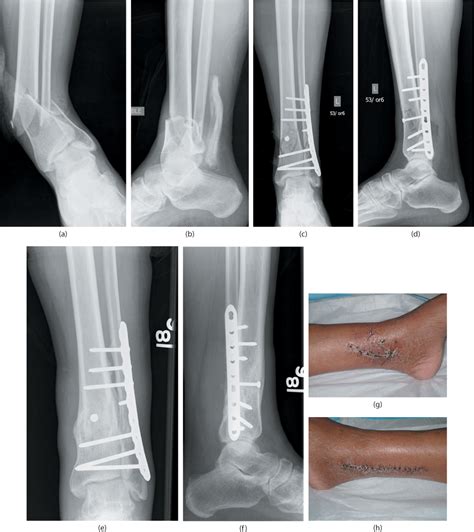

Before we jump into the coding aspects, it’s essential to understand what a distal tibia-fibula fracture actually is. The tibia and fibula are the two long bones in your lower leg. The distal end refers to the part of the bones near your ankle joint. A fracture in this area can range from a hairline crack to a complete break, and it often results from trauma such as falls, sports injuries, or car accidents.

Why is the location so important? Well, fractures in the distal region can be more complex due to the involvement of the ankle joint. These fractures often require surgical intervention to ensure proper alignment and stability. So, when a patient hobbles in with a wonky ankle after a skiing mishap, understanding the nature and location of the fracture is the first step toward accurate diagnosis and treatment.